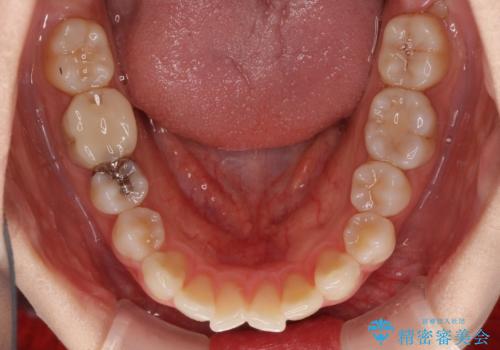

前歯の突出感とデコボコをインビザライン矯正で改善

- 上下前歯の突出感とデコボコを気にして来院された患者様です。

インビザラインによる上下歯列の側方拡大と後方移動、IPR(歯と歯の間を削る)にるスペースの獲得により歯列を整えることとしました。